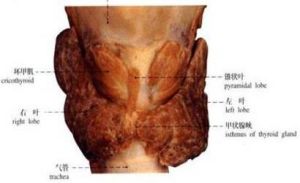

甲狀旁腺

甲狀旁腺

甲狀旁腺

甲狀旁腺